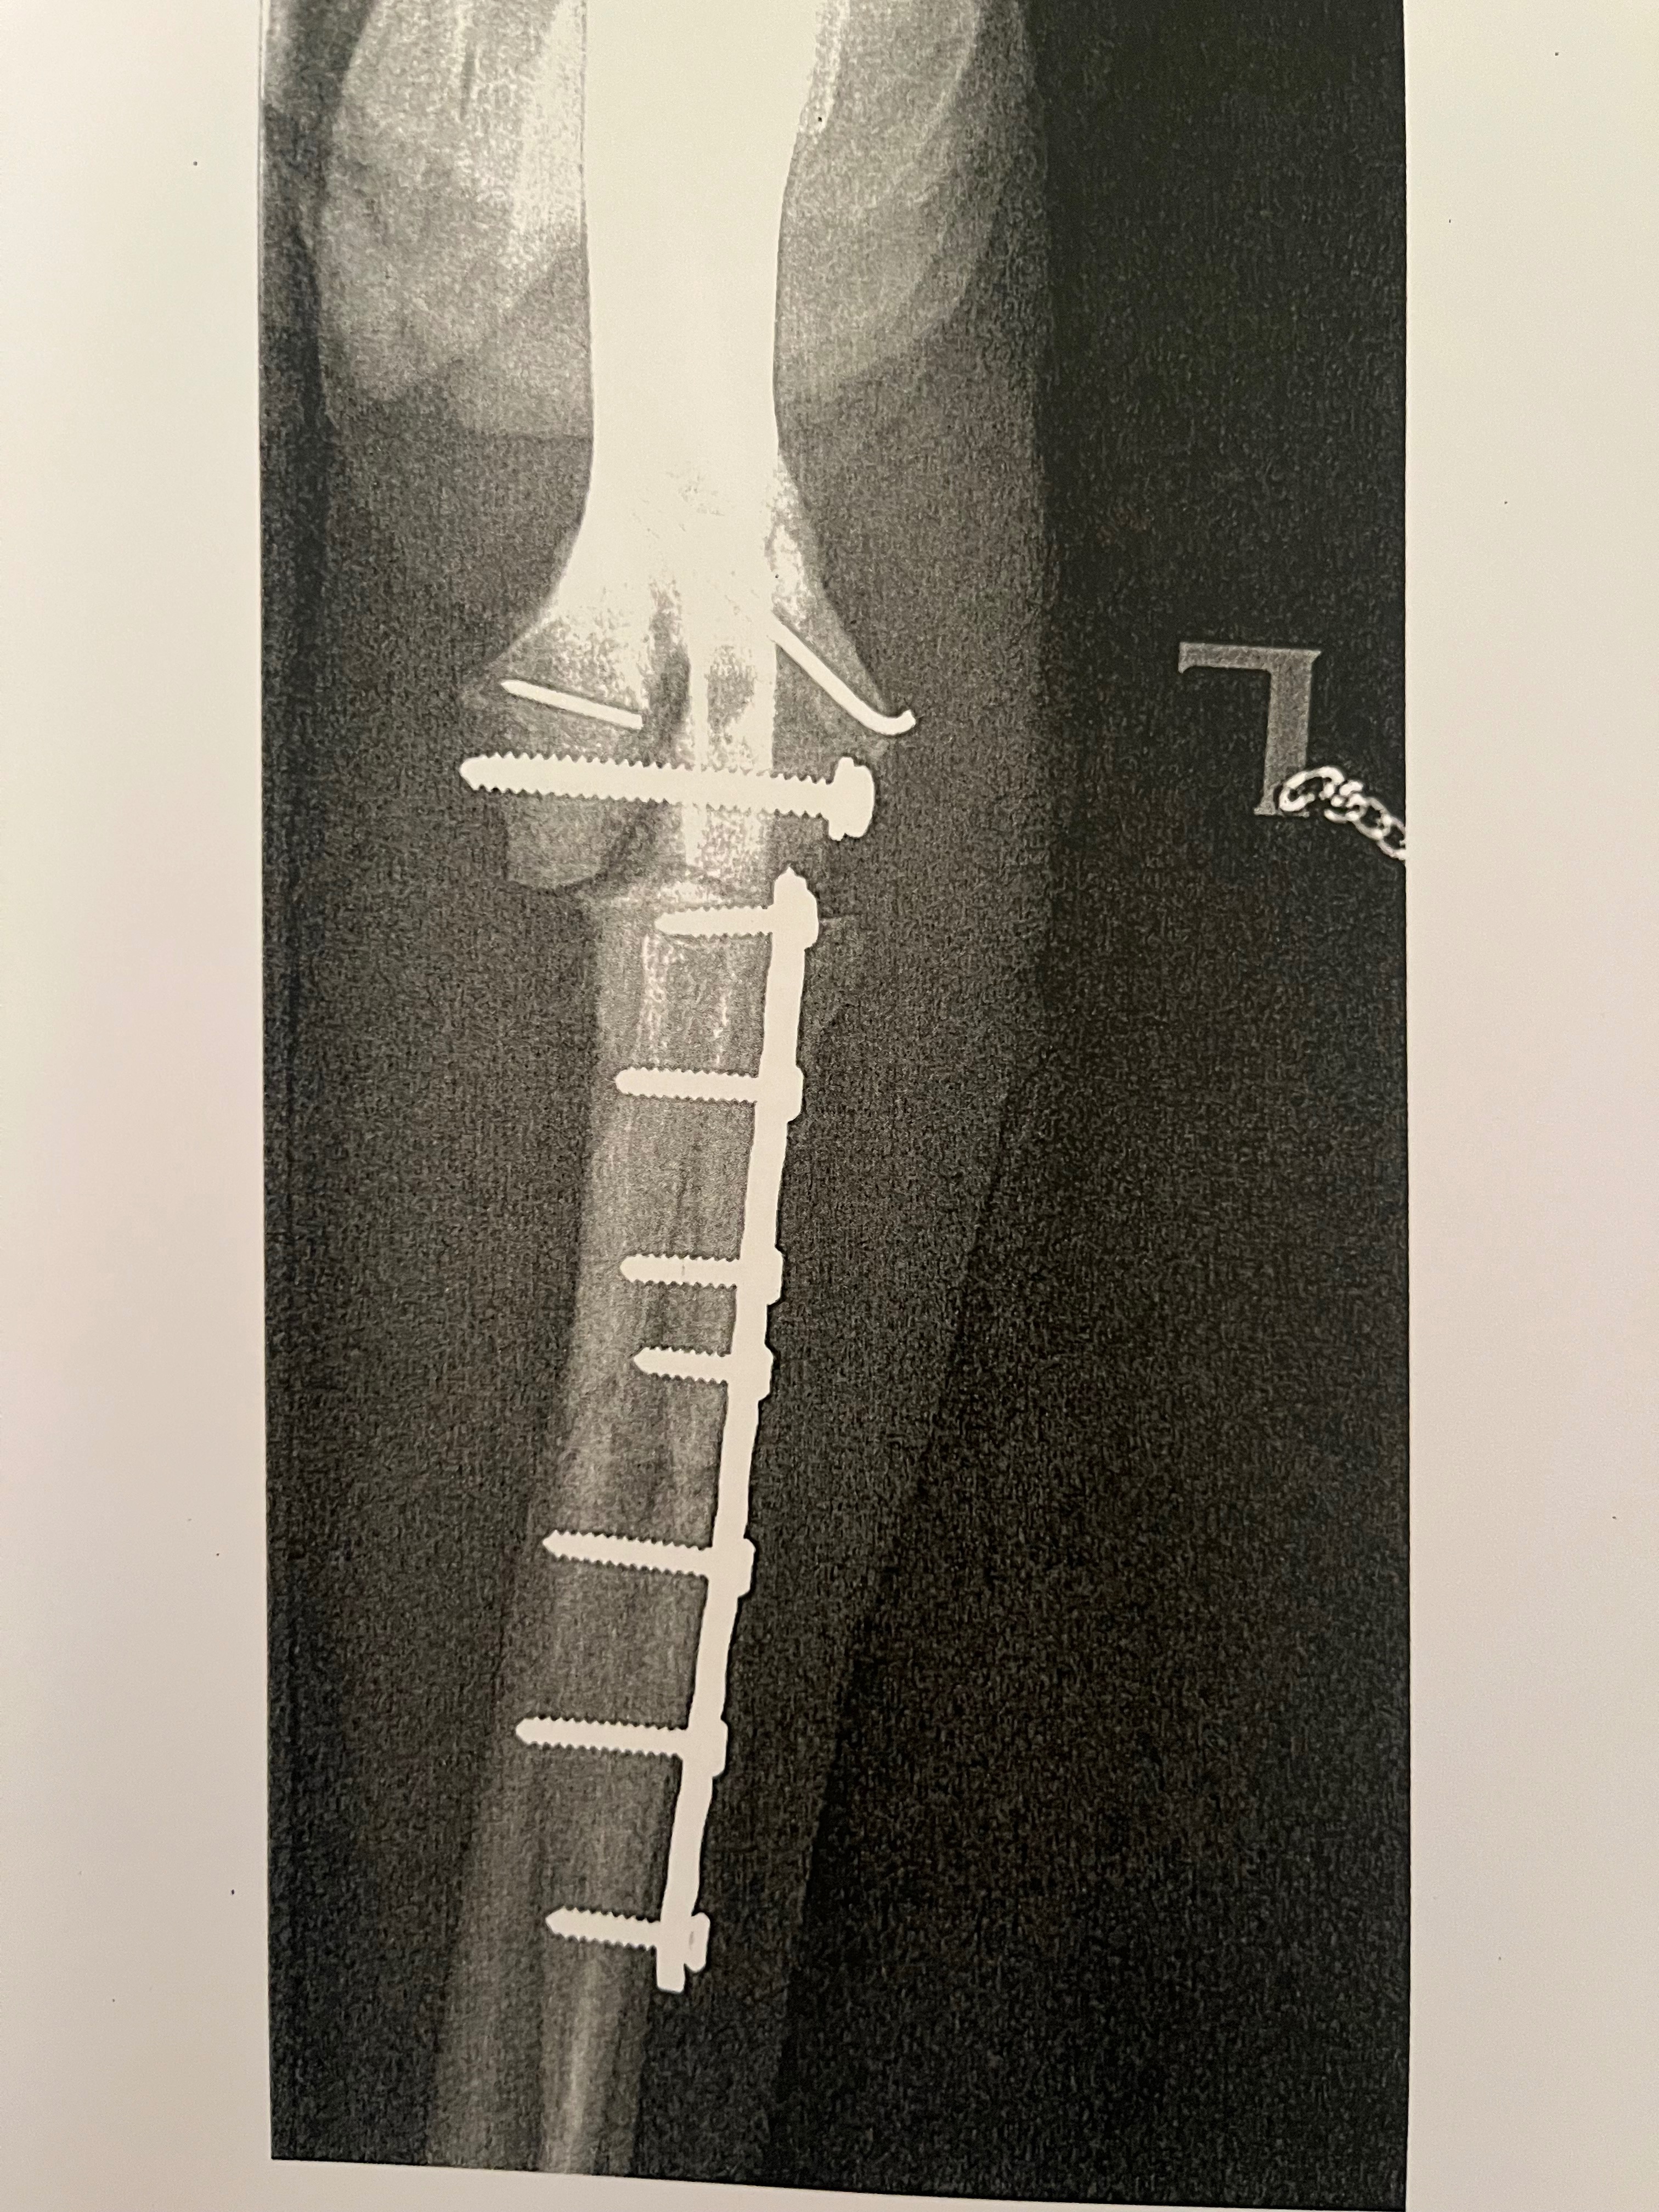

Ende April habe ich mir mein Bein und mein Gelenk am linken Vorderlauf beim Spielen auf dem Feld gebrochen. Es war Freitagnachmittag und wir mussten zur Not Op bis nach Köln fahren, weil es hier in der Umgebung keine Kapazitäten für eine solche Op gab.

Eine Woche nach der Op drangen Drähte durch die Haut aus meinem Gelenk. Für unsere ortsansässige Tierärztin war das nicht typisch, laut Köln aber schon. Also machten wir uns nochmal auf den Weg nach Köln um auf Nummer Sicher zu gehen. Die Oberärztin hat nichtmal den Stützverband abgemacht um sich das Ganze anzuschauen. Lediglich einen Finger unter den Verband gehalten und uns freundlich lächelnd entgegnet: ,,Machen sie sich bitte keine Sorgen, das ist ganz normal.“

Vier Wochen später, Ende Mai, beim Kontrollröntgen wurde dann festgestellt, dass nichts in Ordnung war. Die Drähte haben nicht gehalten und das Gelenk saß nicht dort wo es hingehört. Unsere Tierärztin hat sofort Kontakt zu einer befreundeten Oberärztin (Chirurgin) der Uniklinik Gießen hergestellt. Dort konnte ich schon am nächsten Tag mit einer dicken Schraube re-Operiert werden.

Zu diesem Zeitpunkt war der Knochen im Gelenk aber schon etwas porös. Durch die rausstehenden Drähte der 1. Op sind Keime ins Gelenk eingedrungen. So, dass die neue Schraube im nach hinein auch nicht mehr richtig gehalten hat. In der Uniklinik Gießen haben die Ärzte alles versucht mein Bein zu retten. Weitere Kurznarkosen um das Gelenk immer wieder zu spülen und keimfrei zu bekommen, haben nicht geholfen. Mein Knochen hat immer weiter abgebaut anstatt aufzubauen. Jetzt sehen die Ärzte keine Chance mehr mein Bein zu erhalten.

Ich war ein junger gesunder Hund, der durch eine medizinisch falsche Operationsmethode bei der 1. Op in Köln am Ende sein Bein verliert. An der Uniklinik Gießen sind sich alle Ärzte/Oberärzte (Radiologen/Orthopäden/Chirurgen) einig, die Fraktur im Gelenk wurde in Köln medizinisch falsch rekonstruiert. Dadurch wurden es 3 Monate in denen ich immer schmerzen hatte, fast durchgehend Schmerzmittel und Antibiose bekommen habe, 5 mal sediert war und 24/7 unter Beobachtung stehen musste, damit mir am Ende trotzdem mein Bein amputiert wird.